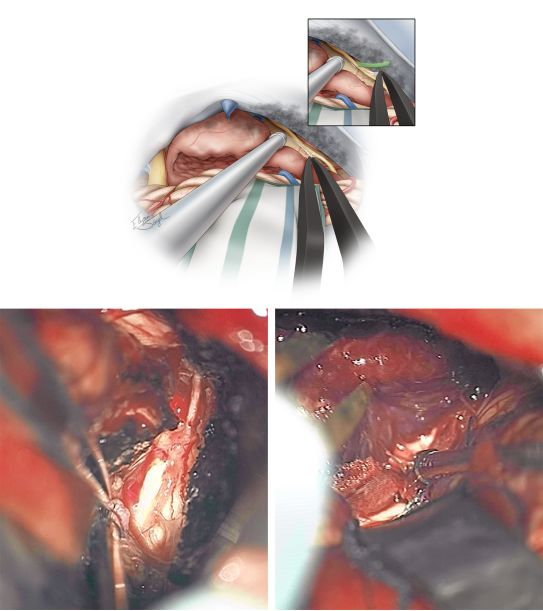

讨论技术原则之前,笔者先展示图1患者术中的一些截图。

图5. 左侧乙状窦后/侧方小脑上入路。注意富血供的岩骨表面硬脑膜(左上图)和小脑幕(右上图),岩上静脉已被切断;三叉神经自肿瘤下极分离(左下图);自小脑幕上肿瘤基底阻断其血供(右下图)。

图6. 典型岩尖脑膜瘤周围相关的神经血管结构示意图,图中展示的包括第V,VII,VIII颅神经。

图7. 处理肿瘤第一个重要步骤是沿着岩骨硬脑膜、岩骨硬脑膜与小脑幕的结合部及小脑幕切断肿瘤血供。在分离肿瘤时岩骨硬脑膜与小脑幕结合处常出血较凶猛(左下图);利用双极电凝耐心止血可以控制出血。第IV颅神经被肿瘤向前推移,需注意保护其不受损伤(右下图)

图8. 分离肿瘤(Dedressing)和阻断肿瘤血供(Devascularization)后需进行肿瘤减压(接下来的"D",Decompression)。可用超声吸引器进行瘤内减压。最初对于肿瘤基底血供的充分阻断有助于此步骤的实施。尽早辨识出肿瘤周围的第V,VII-VIII颅神经有利于更好的保护它们。

图9. 手术的下一步是将肿瘤壁从第V,VII,VIII颅神经和脑干上分离开(Dissection)。用显微镊子分离包绕神经的蛛网膜鞘从而将神经自肿瘤壁上游离(插图),这样做可以避免直接骚扰神经引起的医源性神经损伤。需保留蛛网膜及软脑膜界面。

图10. 沿着小脑幕切迹可以发现牢牢粘在肿瘤前壁上的第IV颅神经。通过小心翼翼且费时的操作,分离出并保留住该细小的神经是可能的,但是很多体积较大的肿瘤已经使得该神经失去功能,即使牺牲掉该神经也不会引起明显的后果。神经的蛛网膜鞘仍可被用于游离该神经(插图)。最下面的照片显示游离出的第IV颅神经走行(左)和分离开的肿瘤壁与脑干(右)